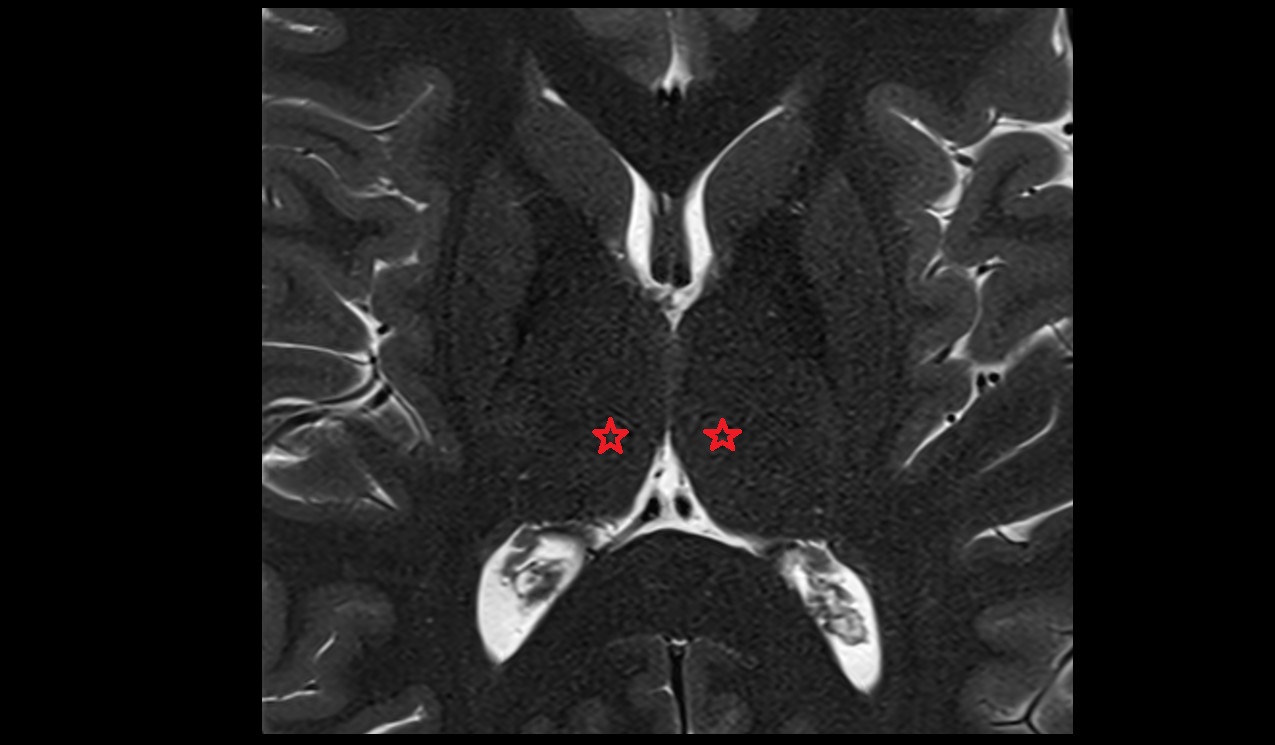

- Dentate nucleus

- Body of hippocampus

- Head of hippocampus

- Tail of hippocampus

- Hippocampus